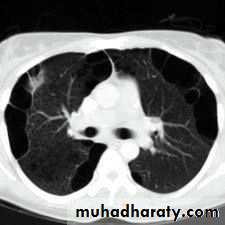

What is the difference??CT scan

BronchoscopyPneumothorax

Emphysema